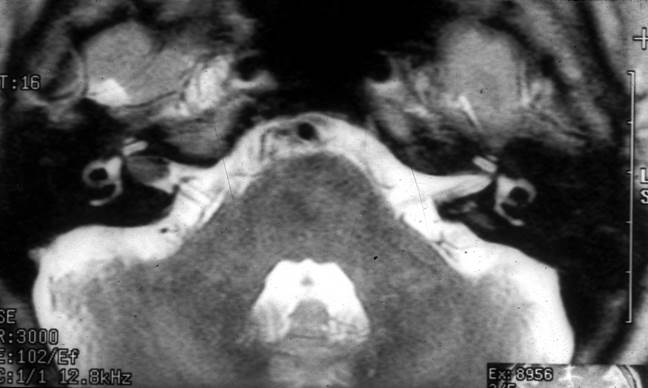

Diagnosis relies on the history and examination with appropriate investigations. An ENT examination and pure tone audiogram along with an examination of the cranial nerves and cerebellar function will often suggest the possibility of a CPA mass. The next examination is an MRI scan. A T2 weighted fast spin echo (T2FSE) or turbo spin echo (T2TSE) protocol can be used to exclude or confirm a tumour whilst a Gadolinium enhanced T1 sequence will give more information about the nature of the lesion. Figures 4 and 5 show typical findings. Diffusion weighted imaging should now also be requested in the diagnostic work up as this sequence can positively distinguish cholesteatoma from other CPA tumours

Figure 4

Two axial MRI scans showing small intra canalicular acoustic neuromas of the right IAM. T2 weighted scan